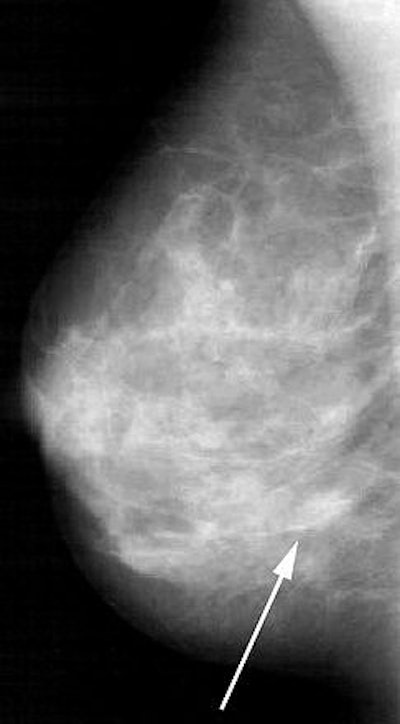

![]() |

| Transverse MR images of the right breast of a woman who underwent MR imaging for screening because of an increased lifetime risk. Unenhanced (above) and contrast-enhanced (below) images show incidental enhancing lesion of 12 mm, rated indeterminate by the radiologist. Images at US performed for correlation showed no abnormalities. At follow-up MR imaging, the lesion was no longer visible. The combined model calculated a 9.7% probability of malignancy. Fig 4a-b. Deurloo, EE, Muller SH, Peterse JL, Besnard APE, Gilhuijs KGA, "Clinically and Mammographically Occult Breast Lesions on MR Images: Potential Effect of Computerized Assessment on Clinical Reading," Radiology doi: 10.1148/radiol.2343031580. Published online January 13, 2005. |

"A point in the lesion detected by the radiologist is first designated manually on the image," the authors said, explaining how the computerized analysis worked. "The system then automatically shifts the designated point to the center of the contrast-enhanced area, and automatically segments the lesion in three dimensions." Morphologic and temporal features in and around this segmented lesion are automatically rated. The probability of malignancy was based on four features: washout, smoothness of contrast material, mean margin sharpness, and variation in margin sharpness.

According to the results, the computerized analysis complemented clinical reading in characterizing lesions that were rated indeterminate or suspicious by the radiologist. A lesion tagged indeterminate by the reader, but marked as malignant by the computerized analysis, had a high probability of malignancy. The same held true for low probability ratings.

While the performance of clinical reading and computerized analysis was identical (area under ROC curve = 0.86 and 0.85, respectively), the combined model proved significantly better (area under ROC curve = 0.91).